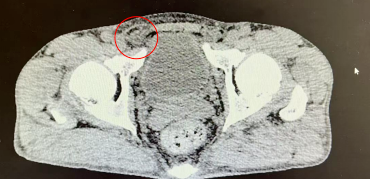

55岁的张先生(化名)身高1.65m,体重56kg。近日,他在洗澡时无意间触摸到右侧腹股沟区有一个核桃大小的包块,不痛不痒,躺下后就会慢慢消失。在北京大学人民医院青岛医院普外科就诊后,被确诊患有右侧腹股沟斜疝。

明确诊断后,普外科团队为张先生进行了全面的术前评估。考虑到他日常活动量大,对术后恢复和生活质量要求较高,团队为他实施了腹腔镜下腹股沟疝无张力修补术。这是一种微创手术,只需在腹部打几个小孔,利用高清腹腔镜找到腹壁的缺损,并使用一张特殊的补片从内部进行加固修补,创伤小,疼痛轻,术后恢复快,复发率也极低。目前患者已顺利出院,对于重返跑步赛道,他表示今后会更加科学地锻炼,注意身体的信号。